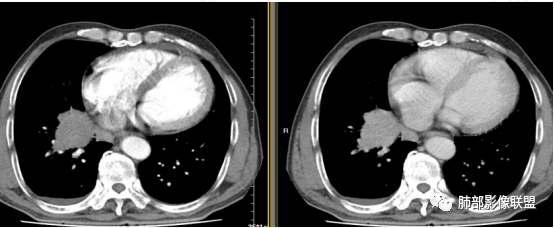

水晶石头:患者中老年男性,咳嗽、咳痰2周。查血常规血象升高。胸部CT:右肺下叶肺门区高密度结块影,部分稍膨隆,部分平直,边界清楚,边缘光滑,增强强化明显。综合考虑良性炎性病变。

赵:右肺下叶内基底段段肿物,b7支气管截断,肿物支气管蔓延生长,增强轻度均匀强化,远端可见坏死考虑鳞癌,右肺门区及纵隔淋巴结肿大转移可能。小细胞肺癌疑点就在右肺门区及纵隔淋巴是不是转移。本例右肺内基底段这么大肿物,如果是小的话,肺门纵隔淋巴结转移是不是小了点。

放射线:右肺下叶内基底段软组织肿块,边界清楚,相对比较圆钝,沿支气管长轴生长,内未见明显的坏死,远端未见阻塞性改变,老年男性,考虑小细胞肺癌>鳞癌。

宇宙:右下肺门肿块,边界清,浅分叶,内侧缘尾巴样凸起,血管间隙生长,延迟强化,其内少许坏死,纵膈淋巴结肿大,右侧少量胸水,考虑小细胞癌、淋巴上皮瘤样癌。

右肺下叶实性病灶,边缘膨隆、分叶、密度相对均匀,增强后渐进性强化,肺门纵隔淋巴结肿大,且主支气管壁增厚。染指标都明显升高,嗜酸性减少至零,考虑感染性病变,需要进一步检查。鉴别淋巴上皮癌。

董金荣:右肺下叶内基底段占位,内基底段支气管截断,前外后基底段血管束受压移位。膨胀性生长,可见分叶,尖角,肿瘤坏死不明显,边缘区看见灶性坏死,逐渐强化。主动脉弓旁及有肺门区及气管隆凸下淋巴结增大。慢性炎性肉芽肿?神经内分泌?鳞癌?

刘悌:右肺下叶近肺门处见类圆形肿块影,其内密度均匀,增强后中度强化,邻近支气管壁浸润性生长,邻近血管包绕,未见狭窄及中断,考虑恶性,淋巴瘤,鉴别腺癌。

(1)病灶形态和分布:双肺散在点片影,可见树芽征。右肺下叶内基底段实性密度团块状影,底部坐落膈面、浅分叶,略呈圆锥形沿血管支气管束探及肺门,可疑“支气管爬行征”。奇食窝区分出子灶。病灶轻中度强化不均,斑片状低密度无强化区,疑坏死,未见钙化。右肺门及淋巴结肿大。

(2)支气管和血管:右肺支气管分支管壁弥漫性增厚,中间段支气管散在结节样凸起,右肺下叶内基底段支气管闭塞,但远端可疑复出。余病灶围绕支气管腔内远端无明显阻塞性不张。内部血管走形自然,提示包绕为主。